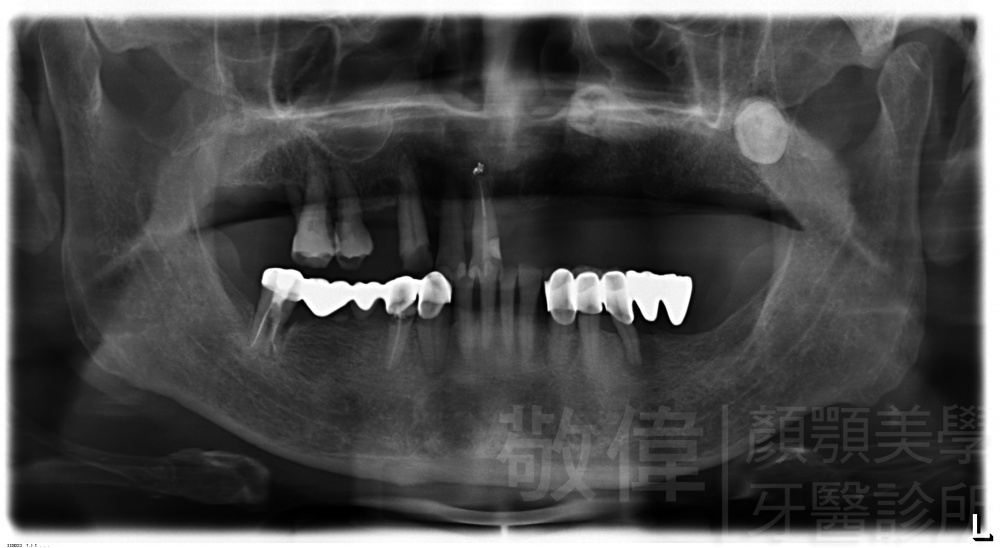

治療前-全口X光   治療後-全口X光